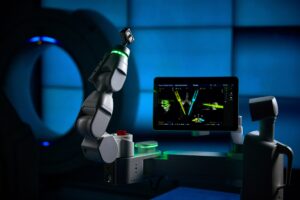

- Robotic technology and Robotic-Guided Surgery

- Robotic Spine Surgery

- Artificial Intelligence Supported Spine Surgery

Robotic-Guided Surgery

This advanced, minimally invasive technique enhances precision and offers a safer, more effective treatment option.

| Robotic-Guided Surgery |

The Benefits of Robotic Spine Surgery

At WVU Rockefeller Neuroscience Institute at Thomas Hospitals, our neurosurgeons are trained to perform robotic spine surgery. This advanced, minimally invasive technique enhances precision and offers a safer, more effective treatment option.

Using a robotic arm and 3D camera, our neurosurgeons can carefully guide surgical instruments with exceptional accuracy. This technology also allows them to create a surgical plan before entering the operating room, ensuring precise placement of hardware and implants through small incisions. This approach can lead to faster recovery, less pain, and reduced risk of complications for patients.

Improved Accuracy

Robotic spine surgery represents a groundbreaking advancement in medical technology. By integrating robotics and navigation technology, our surgeons can achieve exceptional precision, minimizing risks and improving patient outcomes. The ability to meticulously plan and execute procedures enhances both safety and efficiency, making spine surgery less invasive and more predictable.

Advanced Safety

Robotic navigation is a game-changer in spine surgery, significantly reducing radiation exposure by eliminating the need for repeated x-rays. The ability to visualize the spine in real time without requiring a large incision enhances both safety and precision, leading to shorter procedures and improved patient recovery.

Better Outcomes with Faster Recovery Times

By making smaller incisions and minimizing trauma to muscles and tissues, the procedure not only reduces blood loss but also allows for smoother and quicker recovery. Robotic guidance ensures every step follows a precise plan, leading to optimal surgical outcomes.